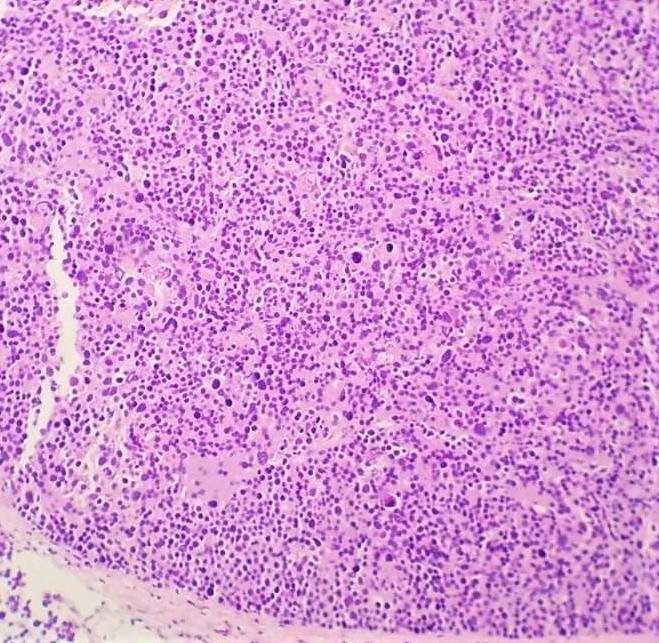

Spermatocytic tumor is a rare germ cell tumor (1-2%) with an average patient age of 55 but does occur in younger individuals such as in this case. Patients often present with testicular swelling with mass. Serum tumor markers are generally not elevated. Macroscopically, these tumors appear as a well-circumscribed tan-grey mass with a bulging surface. Microscopically, these tumors demonstrate a diffuse or sheet-like pattern with edematous stroma and separation by fibrous bands. The tumor is comprised of a polymorphous cell population comprised of 3 main cell types: Small lymphocyte-like cells, intermediate cells and giant cells. Germ cell neoplasia is usually not associated with spermatocytic tumors. The tumor cells are positive for SALL4, CD117, OCT2, CAM 5.2 (40%), and negative for CD30, PLAP, AFP, OCT3/4, D2-40, Glypican-3, EMA, CD30 and Vimentin. The differential diagnosis includes seminoma, embryonal carcinoma (solid pattern) and malignant lymphoma. Radical inguinal orchiectomy is curative with an excellent prognosis.